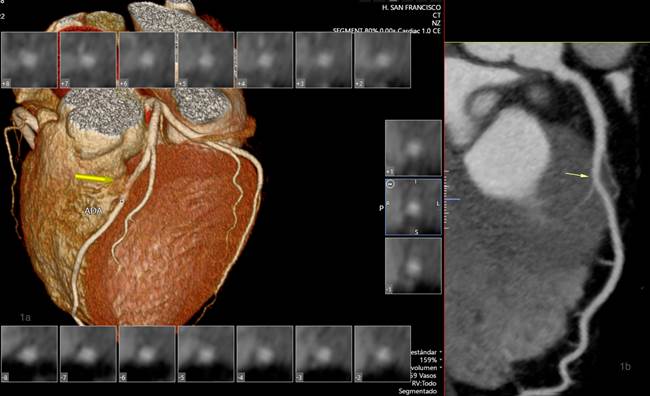

Se aplicó software de cardio-TC usando técnica retrospectiva, en un equipo tomográfico multicorte Cannon Aquilion prime SP160. Se obtuvo el score de calcio en barrido simple y se realizó la adquisición volumétrica del corazón en fase arterial, luego de la administración de 80 ml de medio de contraste intravenoso (Ultravist 370/Iopromida), a una velocidad de 4,5 ml/s, con frecuencia cardiaca de 60 lpm (se administró 50 mg de atenolol oral 1 hora antes y 5 mg de nitroglicerina sublingual 5 minutos previo al estudio). Se realizaron reconstrucciones multiplanares (MPR) y de volumen renderizado (VR) y como resultado se obtuvo: score de calcio Agatston 2 (mínima evidencia de placas calcificadas) y se evidenció un trayecto intramiocárdico a nivel del segmento medial de la arteria descendente anterior. Se midió la profundidad y longitud del PM en vista MPR curvado, en fase 80%, obteniendo como resultado una extensión aproximada de 25 mm y una profundidad de 3,5 mm (Fig. 1).